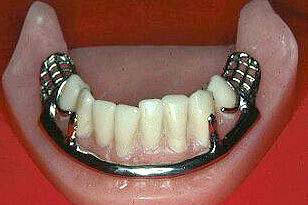

| Banda palatina anterior y posterior

La banda palatina anterior-posterior proporciona

la máxima rigidez y el volumen mínimo.

La fuerza

de este conector se encuentra en el hecho de que la sección anterior y

posterior

se unen entre sí en forma longitudinal con

conectores en ambos lados.

Cada componente se une a conectores menores evitando la

torsión y flexión posible.

Se puede usar en la mayoría de los diseños del maxilar superior.

Es especialmente útil en casos de torus palatino

Debido a la estrechez de los

elementos, las barras deben tener mayor volumen para mantener la rigidez, por lo que

el diseño es más objetable

para el paciente.

Además, los conectores en forma de cincha proporcionan una mayor distribución

de las tensiones en los tejidos palatinos.

- Barra palatina media, muy poco usada porque genera

torsión y se fractura con facilidad Imagen

izquierda

- Placa anterior con

barra palatina posterior, con este diseño se obtiene

máxima estabilidad y rigidez Imagen derecha